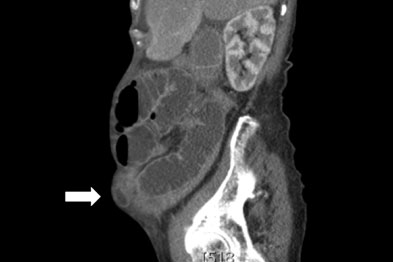

Incarcerated Incisional Hernia Complicated by Abdominal Wall Abscess in an Elderly Patientq The images revealed a suspected incarcerated inci-sional hernia, Semin Ultrasound CT MR. 2004;25:222–238. 3. Aguirre DA, ... Document Retrieval